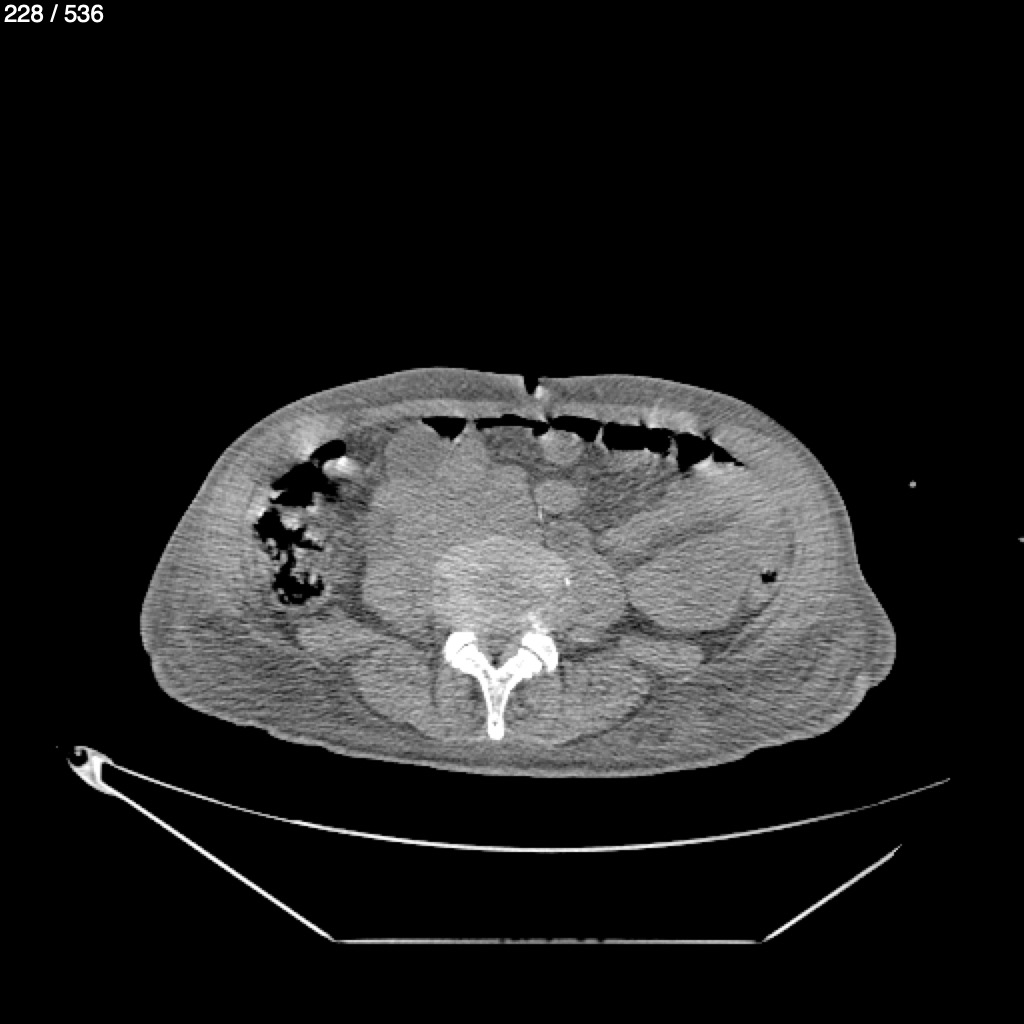

Angel Villalobos Palomeque 73 A - T.C Abdomen Simple